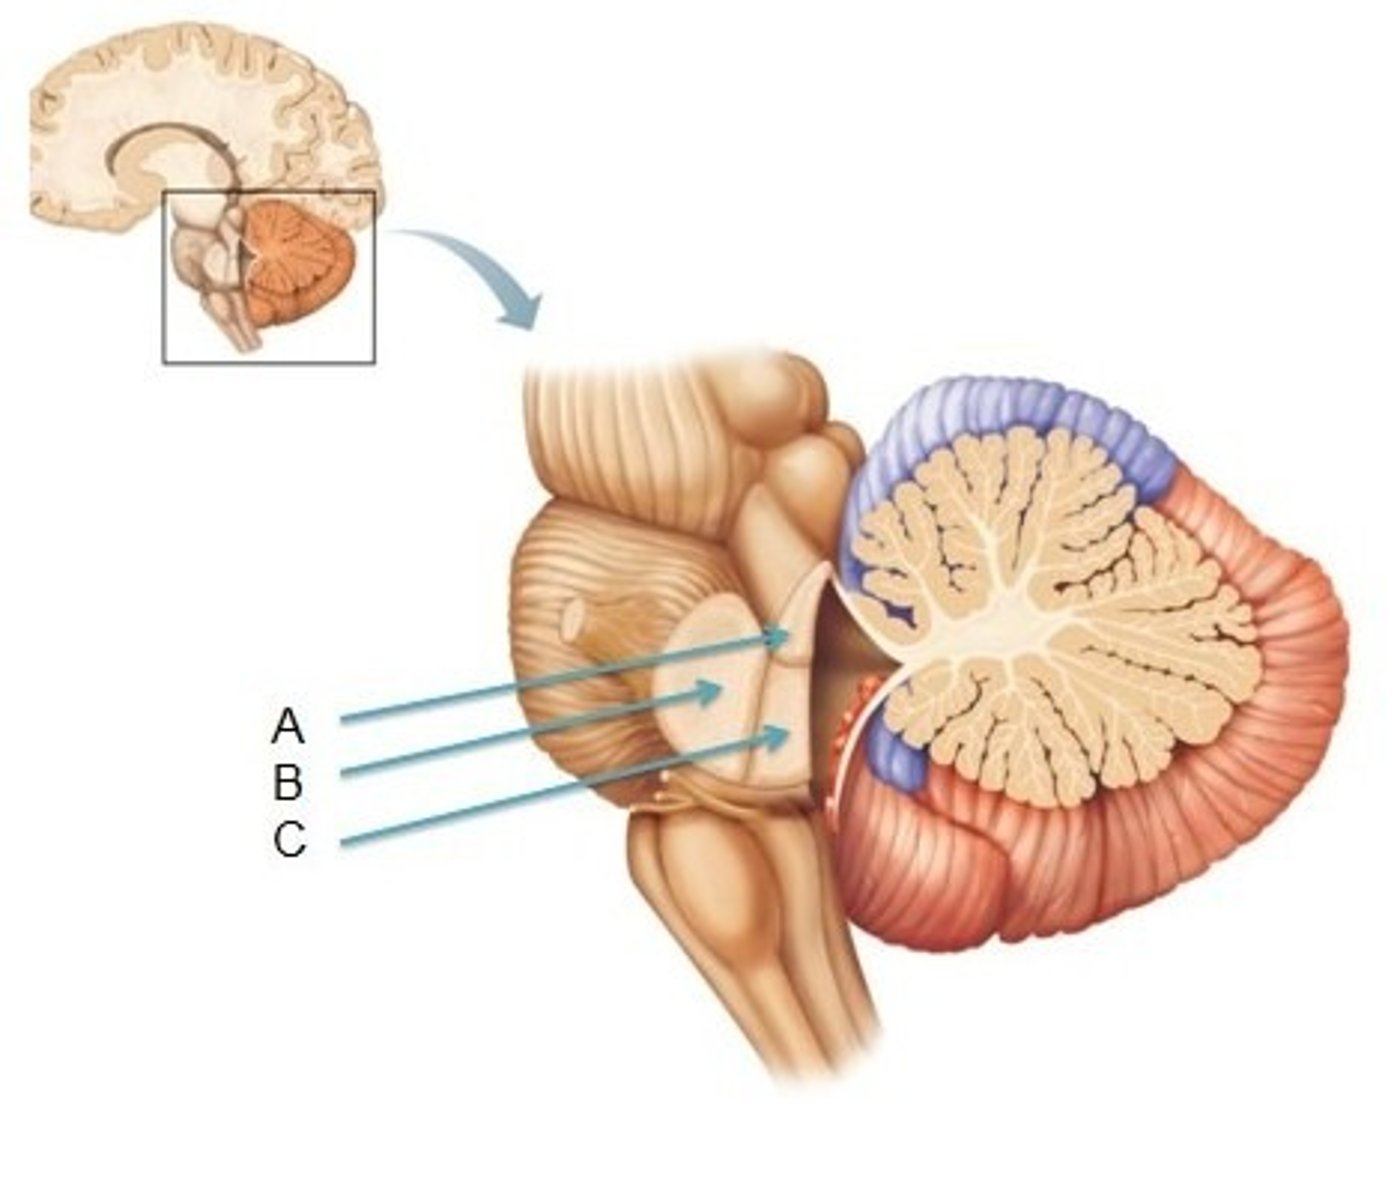

What is the superior boundary of the midbrain?

just under the mamillary bodies of the diencephalon

What is the inferior boundary of the midbrain?

isthmus of brain stem

opening running through the midbrain that separates it into the cerebral peduncles and tectum

cerebral aqueduct (iter or aqueduct of Sylvius)

What does the cerebral aqueduct separate the midbrain into?

cerebral peduncles, tectum

area separating the cerebral peduncles

interpeduncular fossa

Which cranial nerve emerges from the floor of the interpeduncular fossa?

CN III

refers to the ventral part of the cerebral peduncles

columns of white matter that are the corticospinal and corticonuclear (upper motor neuron fibers going to cranial nerve nuclei) running through the midbrain

basis pedunculi (or crus cerebri)

refers to the dorsal part of the cerebral peduncles

tegmentum

(continuous with tegmentum of pons)

part of the midbrain that consists mainly of two (2) pairs of small mounds known collectively as the corpora quadrigemini

tectum

2 pairs of small mounds on the tectum of the midbrain

corpora quadrigemini

ridge of white matter extending laterally from each SUPERIOR colliculus in the corpora quadrigemini of the tectum of the midbrain

superior brachium

What is included in the lower pair of corpora quadrigemini in the tectum of the midbrain?

inferior colliculi

What is included in the upper pair of corpora quadrigemini in the tectum of the midbrain?

superior colliculi

ridge of white matter extending laterally from each INFERIOR colliculus in the corpora quadrigemini of the tectum of the midbrain

inferior brachium

small region located just ventral and rostral to the superior colliculus that is important for the pupillary light reflex

pretectal area

Which cranial nerve emerges just caudal to the inferior colliculus?

CN IV

interpeduncular fossa

cerebral aqueduct

general structure + specific name for this side

cerebral peduncles, basis pedunculi

tegmentum

tectum